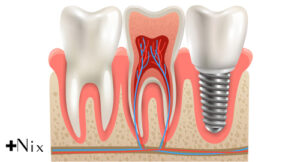

ایمپلنت دندان یکی از روشهای پیشرفته و موثر در جایگزینی دندانهای از دست رفته است. این درمان شامل مراحل کاشت ریشه مصنوعی تیتانیومی در استخوان فک است که پس از جوش خوردن، پایهای محکم برای نصب تاج یا پروتز فراهم میکند. این فرایند باعث بازگرداندن ظاهر طبیعی و عملکرد کامل دندانهای اصلی میشود و تفاوت چشمگیری با روشهای سنتی مثل دندان مصنوعی یا بریج دارد.

با توجه به اینکه کاشت دندان مستقیماً با استخوان فک ادغام میشود، از تحلیل استخوان جلوگیری کرده و به حفظ سلامت دهان و ساختار صورت کمک میکند. اگرچه این روش مزایای فراوانی دارد، نیازمند جراحی تخصصی، هزینه بالاتر و مراقبتهای دقیق پس از عمل است. در این مقاله، مزایا، معایب و نکات مهم درباره ایمپلنت بررسی خواهد شد تا شما تصمیمی آگاهانه بگیرید.

ریشه مصنوعی است که در استخوان فک قرار میگیرد و پایهای برای نصب تاج یا پروتز دندان ایجاد میکند. -